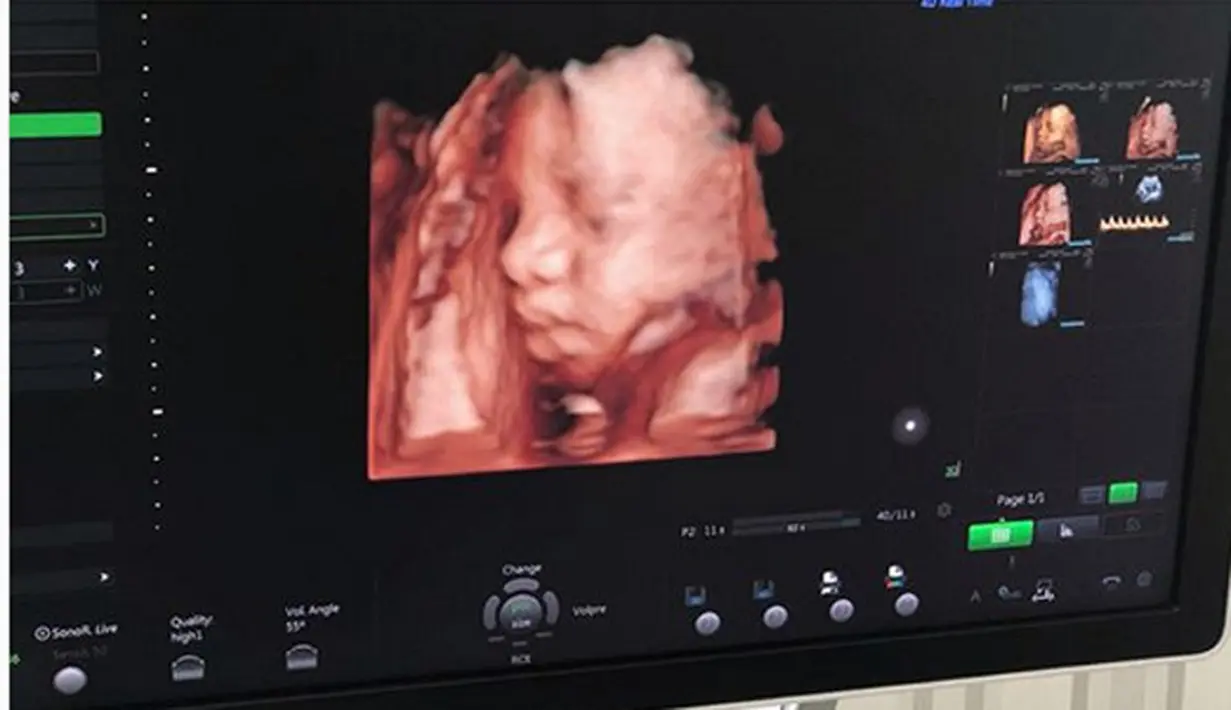

Yang terbaru, bintang sinetron Inikah Rasanya itu baru saja memamerkan USG kandungannya di RS Bunda Jakarta. Menurut prediksi, anak kedua Poppy berjenis kelamin laki-laki. (Instagram/poppybungariphat)

"Alhamdulillah bisa liat muka baby boy sejelas itu pakai 4D π (swipe kekanan ya utk hasil 4d, muka dedenya jelas bgt gemesπ) hidung dan bibirnya sih kamu bgt ya kan?? @fattahriphat π," tulis Poppy. (Instagram/poppybungariphat)

Perempuan 26 tahun itu bersyukur lantaran perkembangan bayi yang ada dalam kandungannya baik. Ia semakin tak sabar ketemu dengan bayi yang diperkirakan laki-laki. (Instagram/poppybungariphat)

"kita lihat hasil akhirnya kaya siapa ya nanti π dan alhamdulillah juga hasil kesehatan dan perkembangan baby sangat baik πͺπ» ga sabarrrrr, bismillah semoga sehat selalu ya anak ibu. Ga sabar bgt ktm km π’," tulisnya. (Instagram/poppybungariphat)